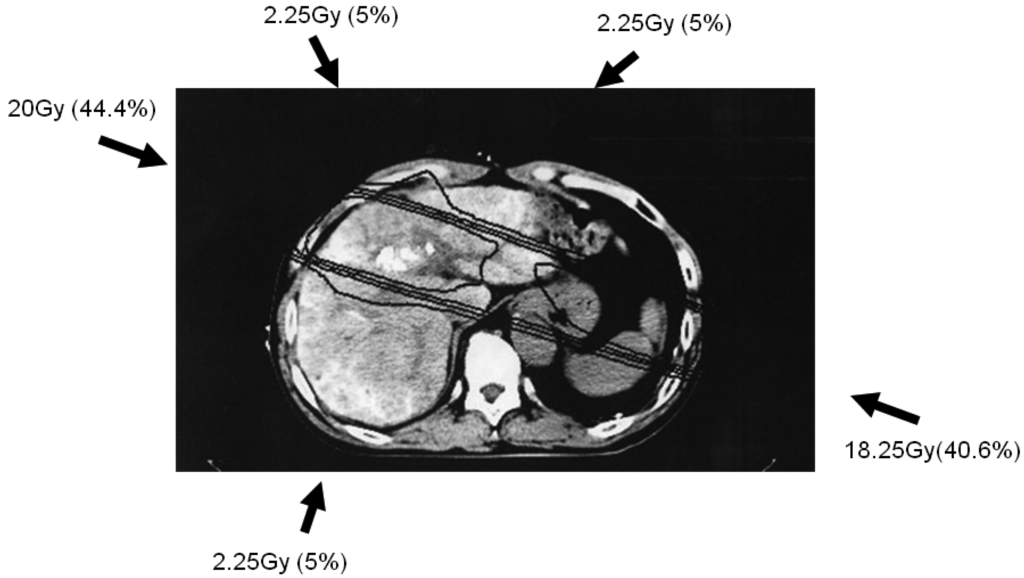

Simulation CT data were transferred to a three-dimensional radiation treatment planning system (Pinnacle, ADAC Laboratories, Milpitas, CA, USA); subsequent CT treatment planning is shown in Figure 1. Clinical target volume (CTV) was defined as main tumor plus PVTT. Planning target volume (PTV) included CTV with a 10-mm margin, accounting for respiratory-induced motion, penumbra covering, and variations in daily setup.

The optimal 3DCRT beam directions (optimal angles of the gantry) were explored using the SPECT images (Figure 2; 1-B, 2-B, 3-B) for guidance. The directions of the two high-dose beams were designed to cover primarily the main tumor and PVTT, and to irradiate FLV as little as possible. As shown in Figure 1, the doses of the high-dose beams were limited to 38.25 Gy/18 fractions/4 weeks to prevent adverse effects to the duodenum, spinal cord, and kidneys [9,10]. Three additional low-dose beams of 6.75 Gy/18 fractions/4 weeks were required to elevate the dose to the CTV, resulting in a total dose of 45 Gy to the isocenter [11]. These low-dose beams were designed to avoid irradiating risk organs such as the stomach, duodenum, and spinal cord. Doses of 2.25 Gy for each additional beam do not cause liver damage even if the beams irradiate FLV. In terms of the kidney, the volume irradiated at 20 Gy or more was planned to not exceed 30% of the total volume. Finally, the couch angle was adjusted to the maximum limit of 90°.